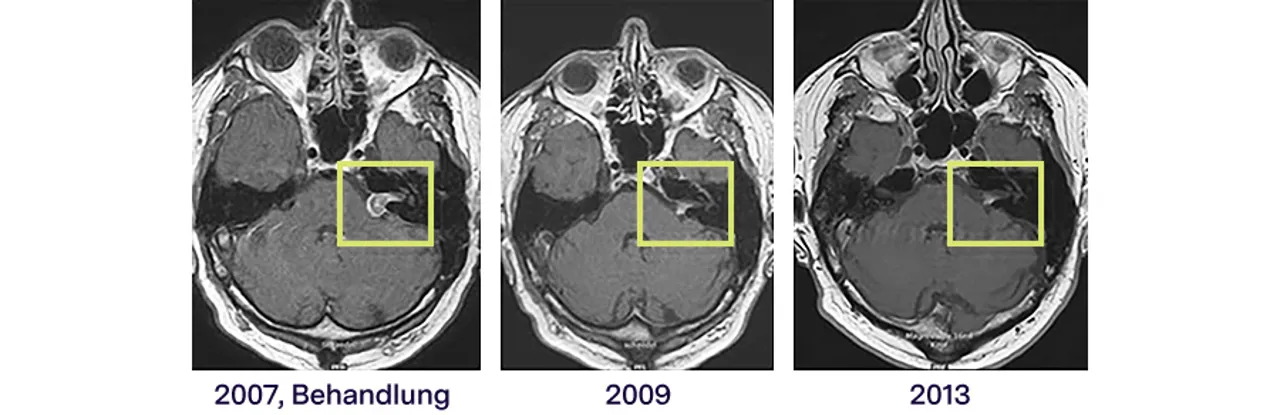

Beispiel einer CyberKnife-Therapie des Akustikusneurinoms im 6-Jahres-Verlauf

Die robotergeführte, radiochirurgische Behandlung hat den Effekt, dass Tumorzellen im Zeitverlauf absterben können. Im MRT ist das gut sichtbar: Im dargestellten Fall konnte mithilfe der CyberKnife-Therapie (2007) nicht nur das Tumorwachstum gestoppt werden, das Akustikusneurinom ist mit der Zeit auch deutlich geschrumpft (Bild Mitte 2009) und im weiteren Verlauf (2013) kaum noch zu sehen (rechts).